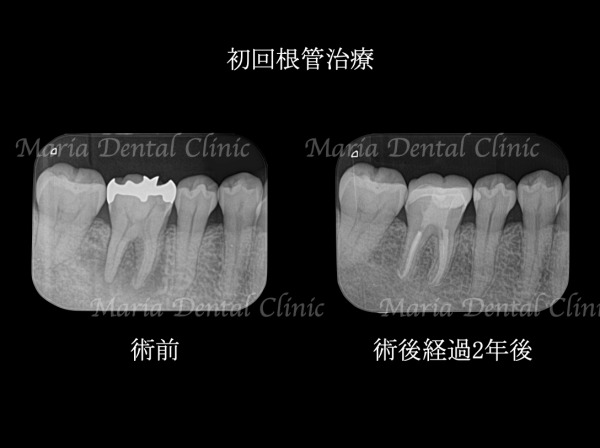

目白マリア歯科の症例

当院では、精密根管治療だけでなく様々な治療の症例を紹介しています。

各分野に特化した歯科医師による、専門的な歯科医療を行っています。